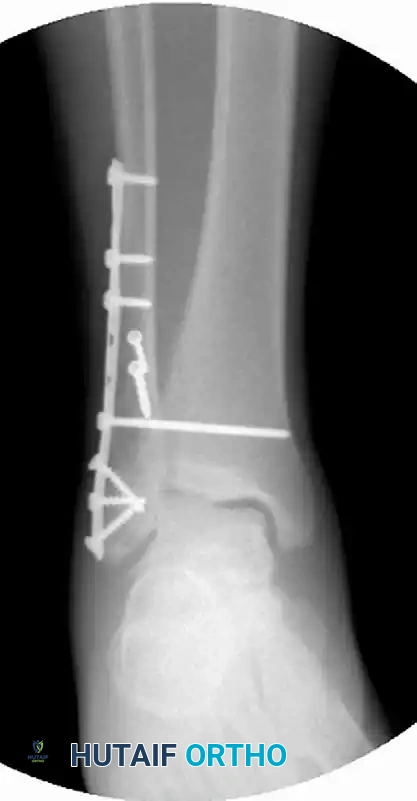

FIGURE 54-7 C: Postoperative Lateral view demonstrating the fibular plate construct and the trajectory of the syndesmotic screw.